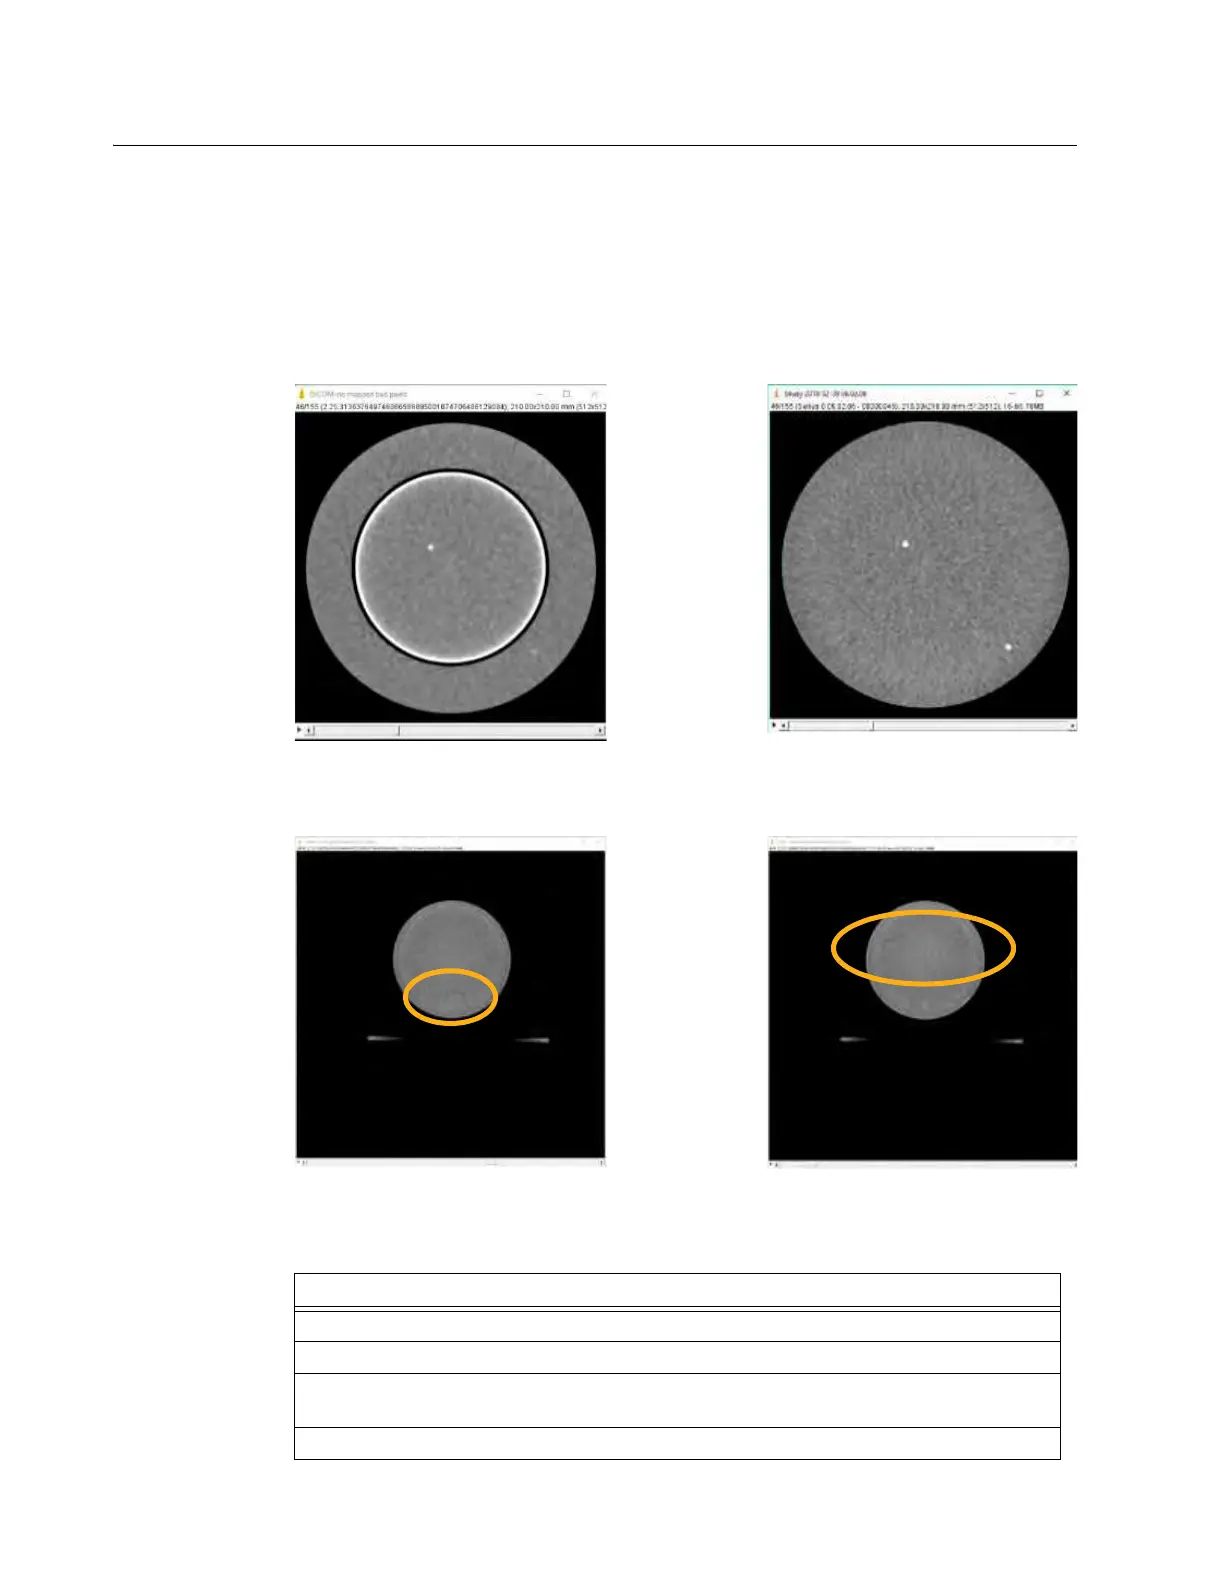

AIRO automatically addresses many bad detector issues. However, for certain detectors issues the

compensation may not be adequate. Consequently, when Gain Calibration identifies a new bad

detector, always review the manual scan results. In the images below, Figure 133 shows the

difference between an unmapped bad detector and a successfully mapped bad detector with the

Gammex 464 Phantom positioned at isocenter. Figure 134 shows images from the phantom

positioned above isocenter that have highlighted residual issues.

Unmapped Bad Detector

Successfully Mapped Bad Detector

Isocenter Artifact in Scan at 75mm

FOV Edge Artifact in Scan at 150mm